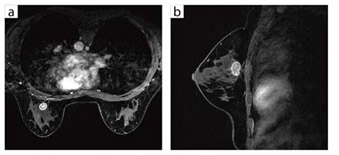

●乳房への臨床応用

![]() 図5 乳がん(8ch ブレストアレイコイル) a:VIBRANT-FLEX(脂肪抑制画像),スライス厚 2mm,1分59秒 b:VIBRANT-FLEX(脂肪抑制画像),スライス厚 2mm,1分46秒 |